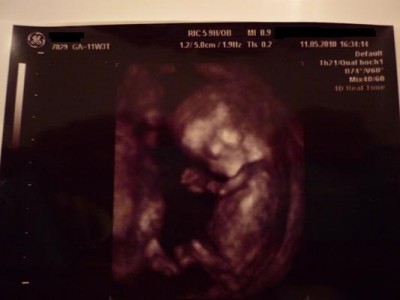

Ich bin echt froh das mein FA immer 3D macht-nun ja außer gestern, warum auch immer!

@conny: Ich stell mal gleich ein Bildchen von unserer Madame rein.Ich wollte getsren eigentlich schon aber war mir doch sehr unsicher da hier leider wieder ein paar negativs reingeflattert sind!